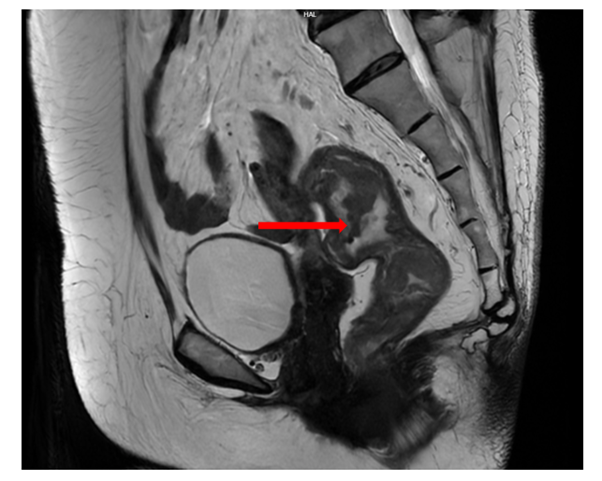

Cộng hưởng từ (MRI) vùng tiểu khung (07/2024):

Hình ảnh dày thành không đều quanh chu vi ở trực tràng cao–đoạn đầu đại tràng sigma; dày nhất khoảng 12 mm, trên đoạn dài khoảng 45 mm; mất cấu trúc lớp thành ống tiêu hóa, kèm thâm nhiễm tổ chức mỡ xung quanh. Lân cận có vài hạch, hạch lớn khoảng 14×9 mm (tổng <7 hạch).

Hình 3: MRI vùng tiểu khung